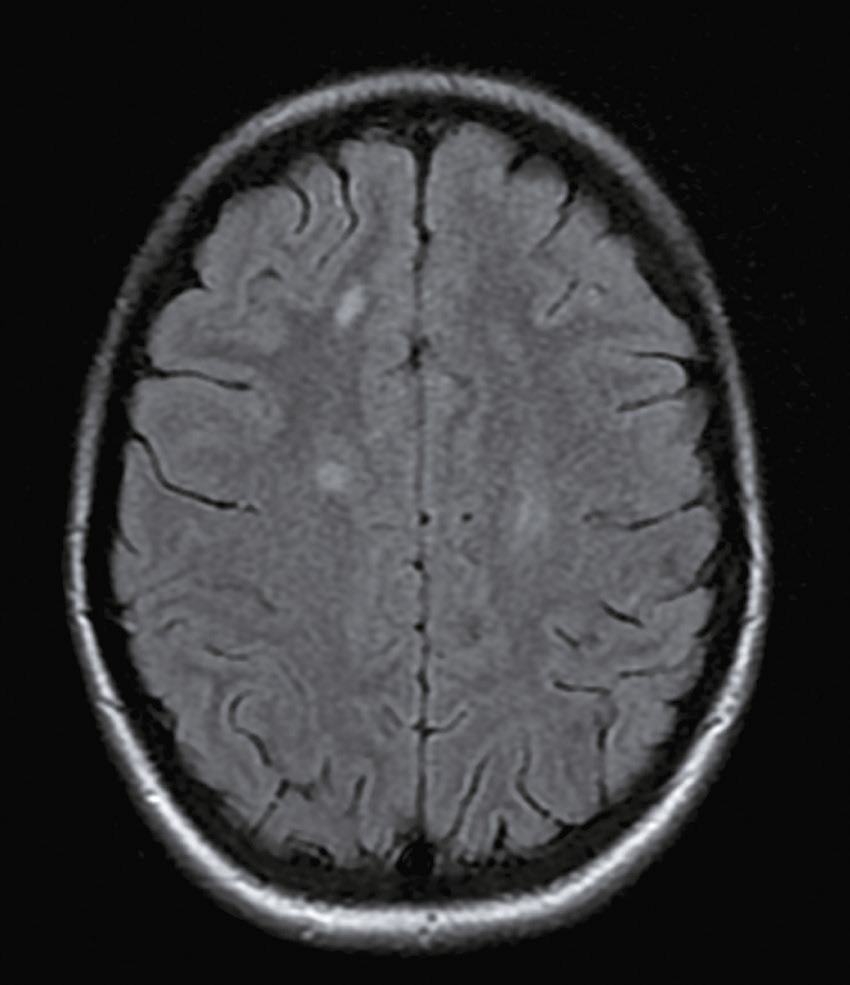

Une nouvelle IRM cérébrale est réalisée devant cette diplopie. Décrivez le cliché (fig. 31.1).

L'image montre une coupe transversale d'un cerveau humain obtenue par imagerie par résonance magnétique (IRM). Cette image est une vue axiale, ce qui signifie qu'elle est prise horizontalement à travers le cerveau. On peut observer les différentes structures cérébrales, y compris la matière grise et la matière blanche. Les ventricules latéraux, qui sont des cavités remplies de liquide céphalo-rachidien, sont visibles au centre de l'image. Les zones plus claires autour des ventricules peuvent indiquer des anomalies ou des lésions, souvent associées à des conditions neurologiques comme la sclérose en plaques. Les contours du cerveau sont bien définis, et les différentes régions du cortex cérébral sont clairement visibles. Cette image est intéressante car elle permet aux médecins de diagnostiquer et de surveiller diverses maladies neurologiques en visualisant les structures internes du cerveau avec une grande précision. L'IRM est une technique non invasive qui utilise des champs magnétiques et des ondes radio pour produire des images détaillées des organes et des tissus internes, ce qui est crucial pour la détection précoce et le traitement des maladies cérébrales.

- C hypersignaux de la substance blanche périventricu-laire

- D hypersignaux du tronc cérébral

- E hypersignaux juxtacorticaux